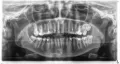

Мне 21 год. Ранее проблем с зубами не было. Недавно обнаружила на обоих нижних зубах, кажется, под номером шесть, абсолютно симметричные отверстия. Располагаются прямо в середине, с "лицевой стороны", если можно так выразиться, не сверху. Отверстия небольшие, почти идентичны, по цвету не отличаются от остальных зубов, и поэтому были обнаружены случайно. Возникает ощущение, будто кто-то взял и просверлил два этих зуба.

Является ли это серьезным поводом обратиться ко врачу?